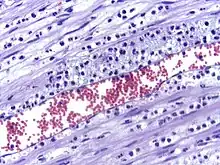

The cytoskeletons of the leukocytes are reorganized in such a way that the leukocytes are spread out over the endothelial cells. In this form, leukocytes extend pseudopodia and pass through gaps between endothelial cells. This passage of cells through the intact vessel wall is called diapedesis.[3] These gaps can form through interactions of the leukocytes with the endothelium, but also autonomously through endothelial mechanics.[4] Transmigration of the leukocyte occurs as PECAM proteins, found on the leukocyte and endothelial cell surfaces, interact and effectively pull the cell through the endothelium. Once through the endothelium, the leukocyte must penetrate the basement membrane. The mechanism for penetration is disputed, but may involve proteolytic digestion of the membrane, mechanical force, or both.[5] The entire process of blood vessel escape is known as diapedesis. Once in the interstitial fluid, leukocytes migrate along a chemotactic gradient towards the site of injury or infection.